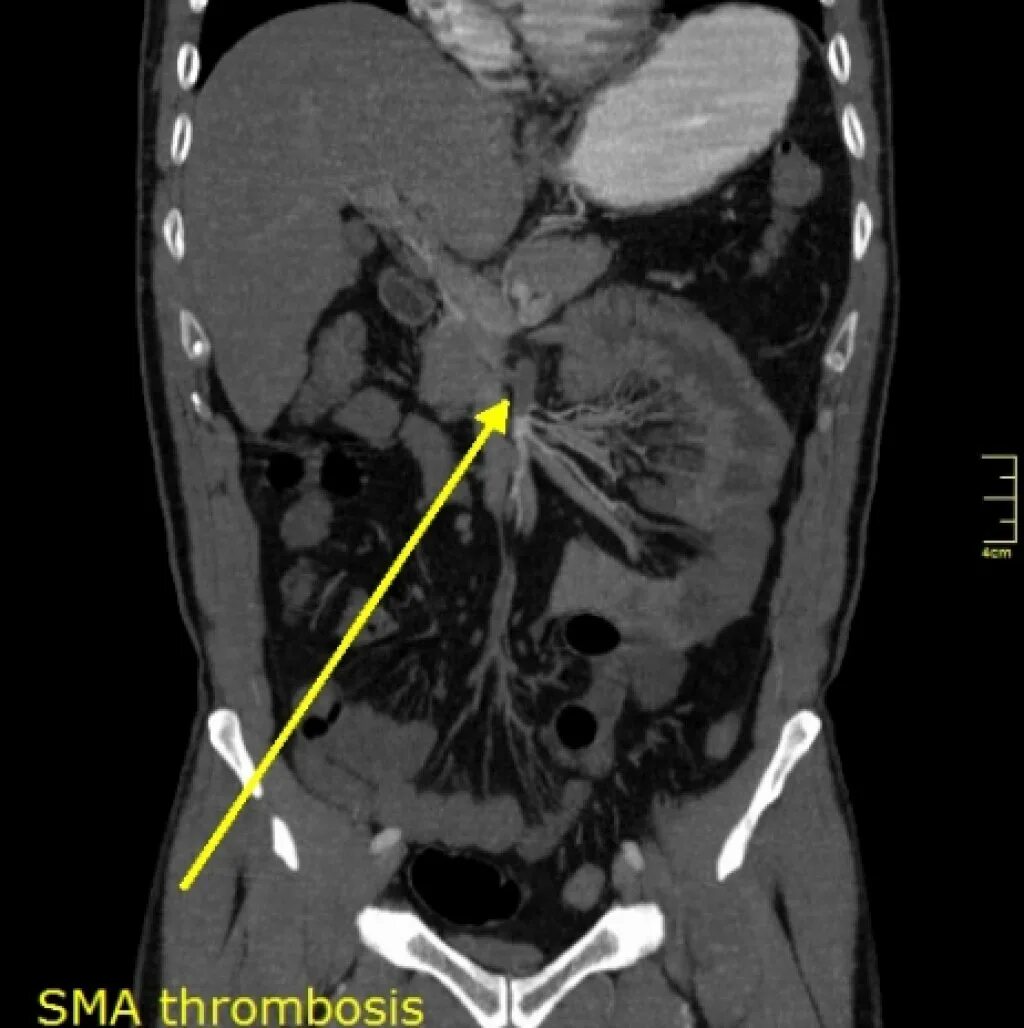

Тромбоз брыжеечной артерии